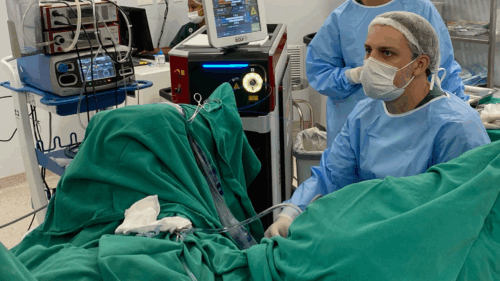

“O HoLEP é uma cirurgia minimamente invasiva feita por via uretral, sem cortes externos. Usamos um laser de Hólmio para separar e remover o tecido interno da próstata que está causando a obstrução, como se descascássemos a parte interna de uma fruta”, explica o Dr. Leonardo. Esse tecido é empurrado para a bexiga e removido por um equipamento chamado morcelador, que o fragmenta e aspira.

O laser de Hólmio é o principal diferencial do HoLEP. Ele permite cortes precisos com excelente coagulação, reduzindo sangramentos e tempo cirúrgico. O procedimento conta ainda com equipamentos como o ressectoscópio, que permite visualização interna, e o morcelador, responsável por aspirar o tecido removido.

Contudo, o Dr. Leonardo alerta: “O HoLEP exige treinamento especializado e experiência. Nem todo urologista está habilitado para essa técnica. Na UROBH, investimos constantemente na formação da equipe e na atualização tecnológica para garantir o melhor resultado aos pacientes.”